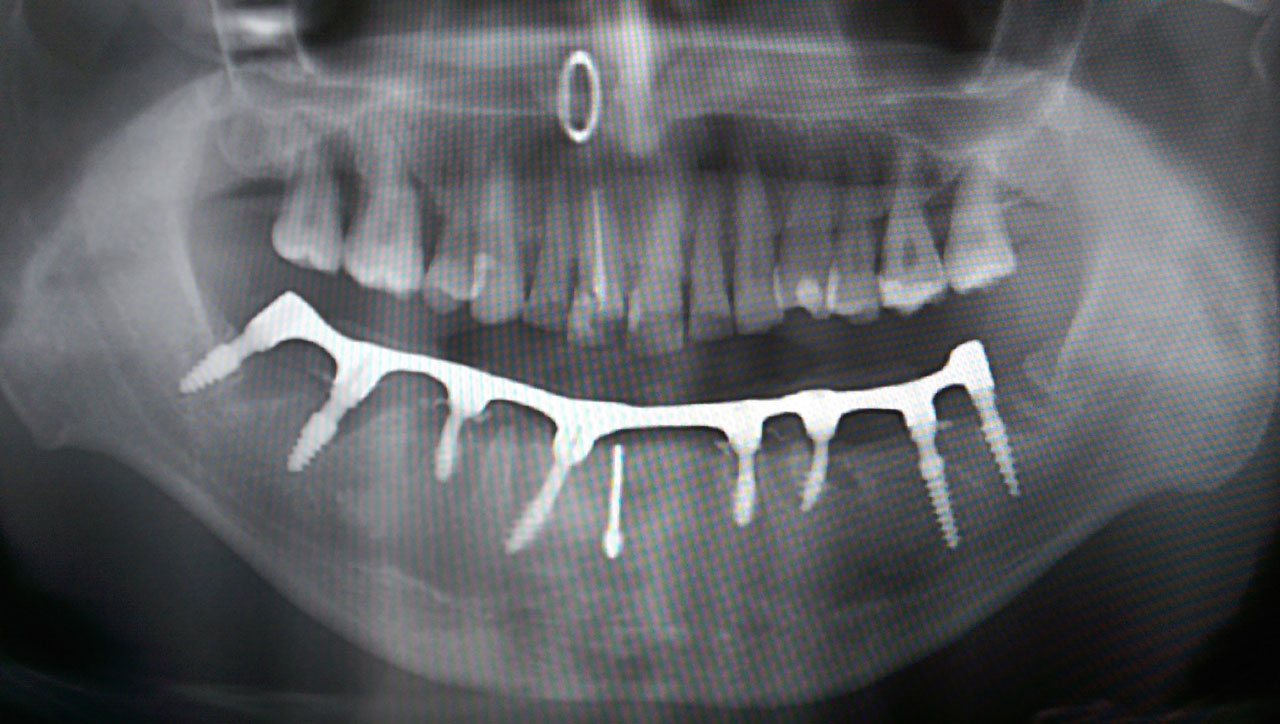

Alsó állcsont teljes rehabilitációja 72 óra alatt

Alsó állcsont teljes rehabilitációja 72 óra alatt, azonnal terhelhető implantátumokkal súlyos paradontitisben szenvedő dohányzó páciens esetében. Az alsó állcsont fogai mind mozogtak az előrehaladott fogágypusztulás miatt.

A fogakat eltávolítottuk, a gyulladt, fertőzött csontot kitakarítottuk, kifertőtlenítettük, majd azonnal implantáltunk.

Svájci, IHDE márkájú, azonnal terhelhető implantátumokat helyzetünk be, és ezekre harmadnapra rögzített, hosszútávú, fémvázas, esztétikus műanyaggal leplezett hidat ragasztottunk be.

Ezt az ideiglenes hidat a sebek gyógyulása miatt használjuk, de tartóssága miatt véglegesként is használható.

A legtöbb esetben, ahogy itt is, 6 hónap múlva porcelán hídra cseréljük, a teljes gyógyulás után.